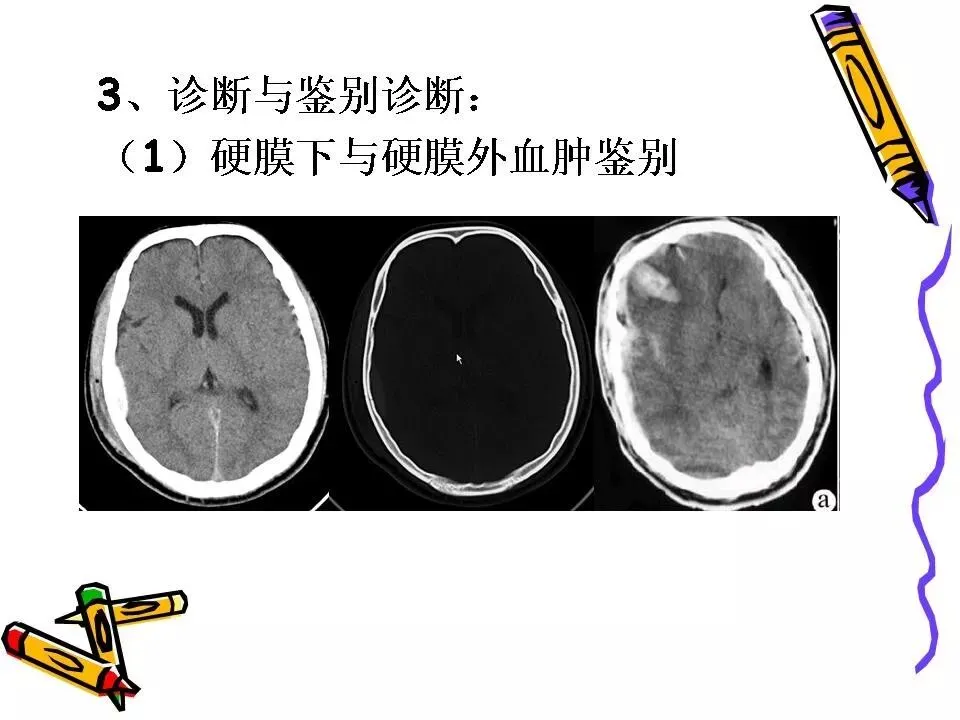

>常见颅脑外伤CT诊断(PPT)

常见颅脑外伤CT诊断(PPT)